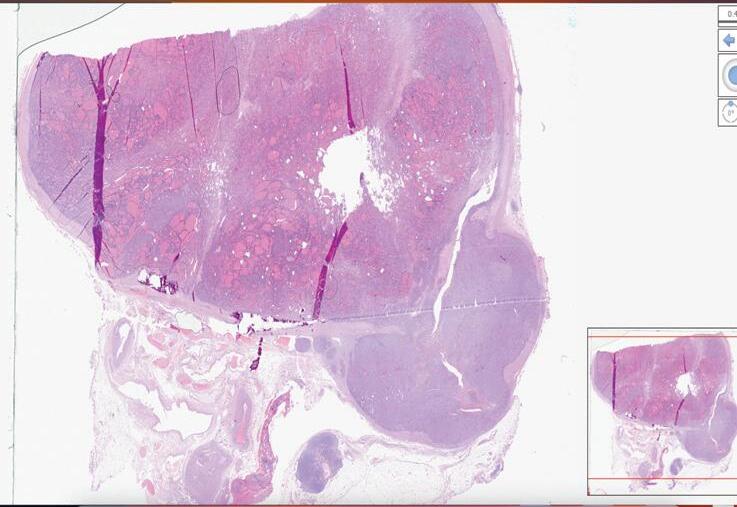

LA DIGITAL PATHOLOGY COME STRUMENTO DI UNIFORMITÀ DI DIAGNOSI PATOLOGICA: Il PROGETTO ITCO

Anna Crescenzi, Giovanni Tallini, Cira di Gioia